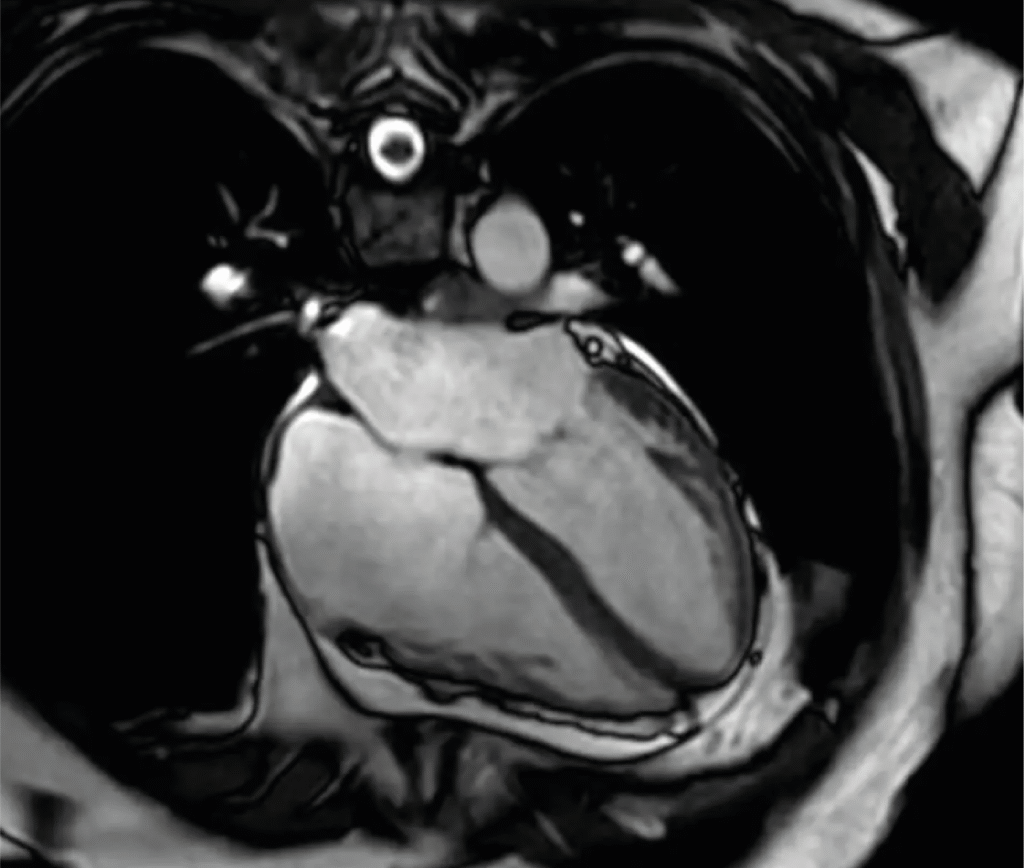

Cardiac MRI

A non-invasive, radiation-free imaging technique that offers in-depth visualization of heart muscle, valves and blood flow. It's especially useful for diagnosing cardiomyopathies and congenital heart diseases.